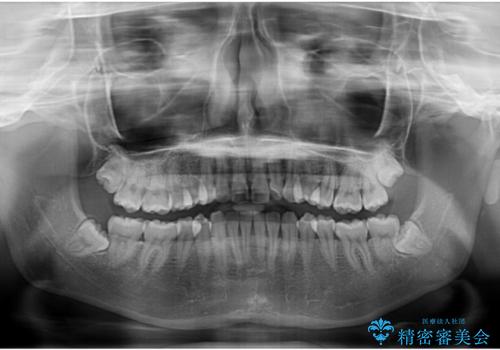

左上の前歯が出ているのが気になる 審美装置による非抜歯ワイヤー矯正

- 左上の前歯が出ていることを主訴として来院された患者様です。

当初はインビザラインを希望されていましたが、職業柄お茶する機会が多く装着時間を確保することが難しいとのことで、相談の上ワイヤー矯正の中では目立ちにくい審美装置で矯正を進めていくこととしました。

1年と少しで矯正治療を終えることができ患者様は大変満足されました。